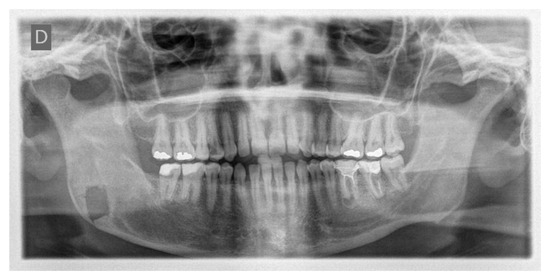

6. Case 4: Removal of Recurrent Ameloblastoma at the Mandibular Angle

A 32-year-old patient came to our attention during an oncological follow-up, which included the execution of an OPT (Orthopantomography) X-ray, revealing a new osteolytic lesion at the right mandibular angle. In 1996, the patient underwent surgical removal of a unicystic ameloblastoma in a different hospital. We reviewed the patient’s most recent radiological documentation, which was an OPT X-ray taken 12 years earlier (8 years after the initial surgery) showing no mandibular lesions. A mandibular CT scan was requested to better define the lesion (Figure 12).

In light of the suspicion of an ameloblastoma recurrence, surgical removal was recommended, opting for the use of tracked instruments with surgical navigation. A maxillary bite was created, followed by the attachment of 5 screws with varying spatial orientations that would function as fiducial markers. This bite was employed to maintain the mandible in a consistent position both during the preoperative CT scan acquisition and throughout the entire surgical procedure (Figure 13).

During the surgical procedure, the Dynamic Reference Frame (DRF) was positioned in the right parietal bone, and the positions of the screws on the bite were recorded as fiducial markers. The same bite used during the CT image acquisition was utilised for this purpose. The navigation accuracy was less than 0.5 mm. The piezoelectric was registered by attaching a tracking tool with three reflective spheres to the handpiece, and the tip of the piezoelectric was marked and utilised as a reference point for navigation. The navigation accuracy was found to be less than 1 mm.

Under the guidance of the tracked piezoelectric device, the resection of the lesion was carried out as per the preoperative plan, with macroscopically preserved healthy bone margins, including the lower and posterior mandibular border (Figure 14).

The day following the surgery, a follow-up OPT X-ray was requested, which displayed the resection area and the integrity of the lower and upper borders of the mandible, in accordance with the preoperative virtual planning (Figure 15).

The histological examination of the surgical resection confirmed the diagnosis of a recurrent unicystic ameloblastoma.

To date, the patient undergoes annual consultations in our department with OPT X-rays, with a follow-up duration of 9 years, and no new recurrence has been detected.